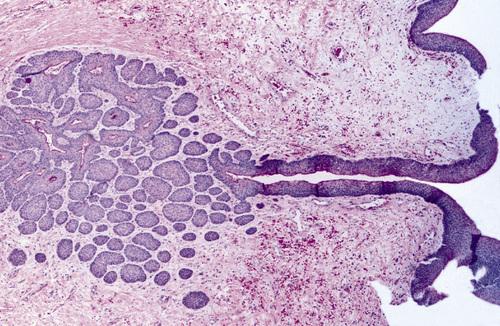

Odontogenic keratocyst (OKC) showing numerous odontogenic epithelial rests in the cyst wall.

nevoid basal cell carcinoma syndrome